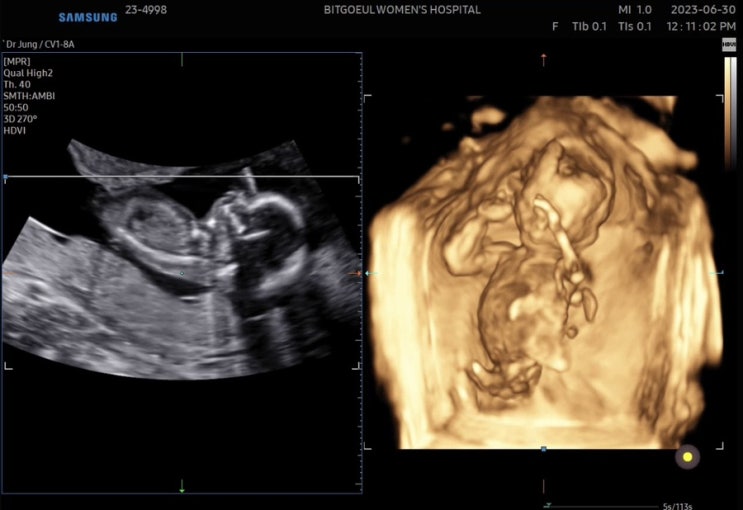

15주 - 2차 기형아검사, 성별 확인?

4주간의 긴 기다림... 끝에 15주 2일에 2차기형아검사와 진료를 보았다. 11:30 쯤 접수했더니 대기가 약간 ...